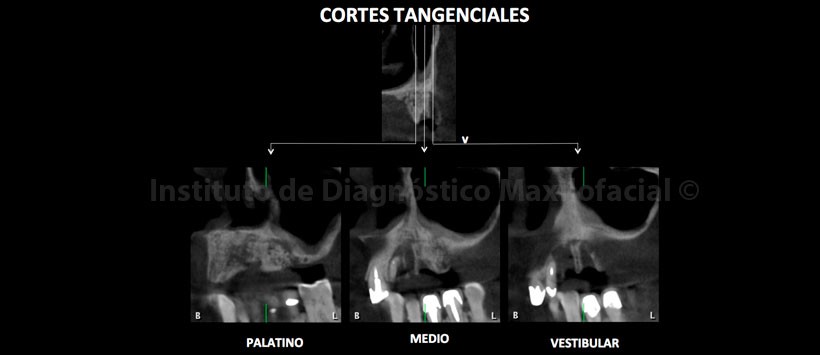

A la evaluación de la tomografía volumétrica (CBCT) en los cortes axiales (Figura 2, 3), coronales (Figura 4,5), transaxiales (Figura 6,7) y tangenciales (Figura 8), se aprecia proceso osteolítico de límites mal definidos, bordes difusos, localizado a nivel del maxilar superior del lado izquierdo, que se extiende en sentido mesio-distal desde la pieza 2.2 hacia los lechos alveolares de las piezas 2.3 y 2.4 y en sentido cefálico-caudal de la címa de reborde alveolar hasta el piso del seno maxilar a nivel de la zona de pieza 2.5. Se aprecia, presencia de secuestros óseos y reacción periostal en la tabla ósea vestibular y en zona del piso del seno maxilar.

En las reconstrucciones 3D se representa la lesión ósea que involucra los lechos alveolares de piezas 2.3 y 2.4 y además la presencia de secuestros óseos (Figura 9,10 y 11).